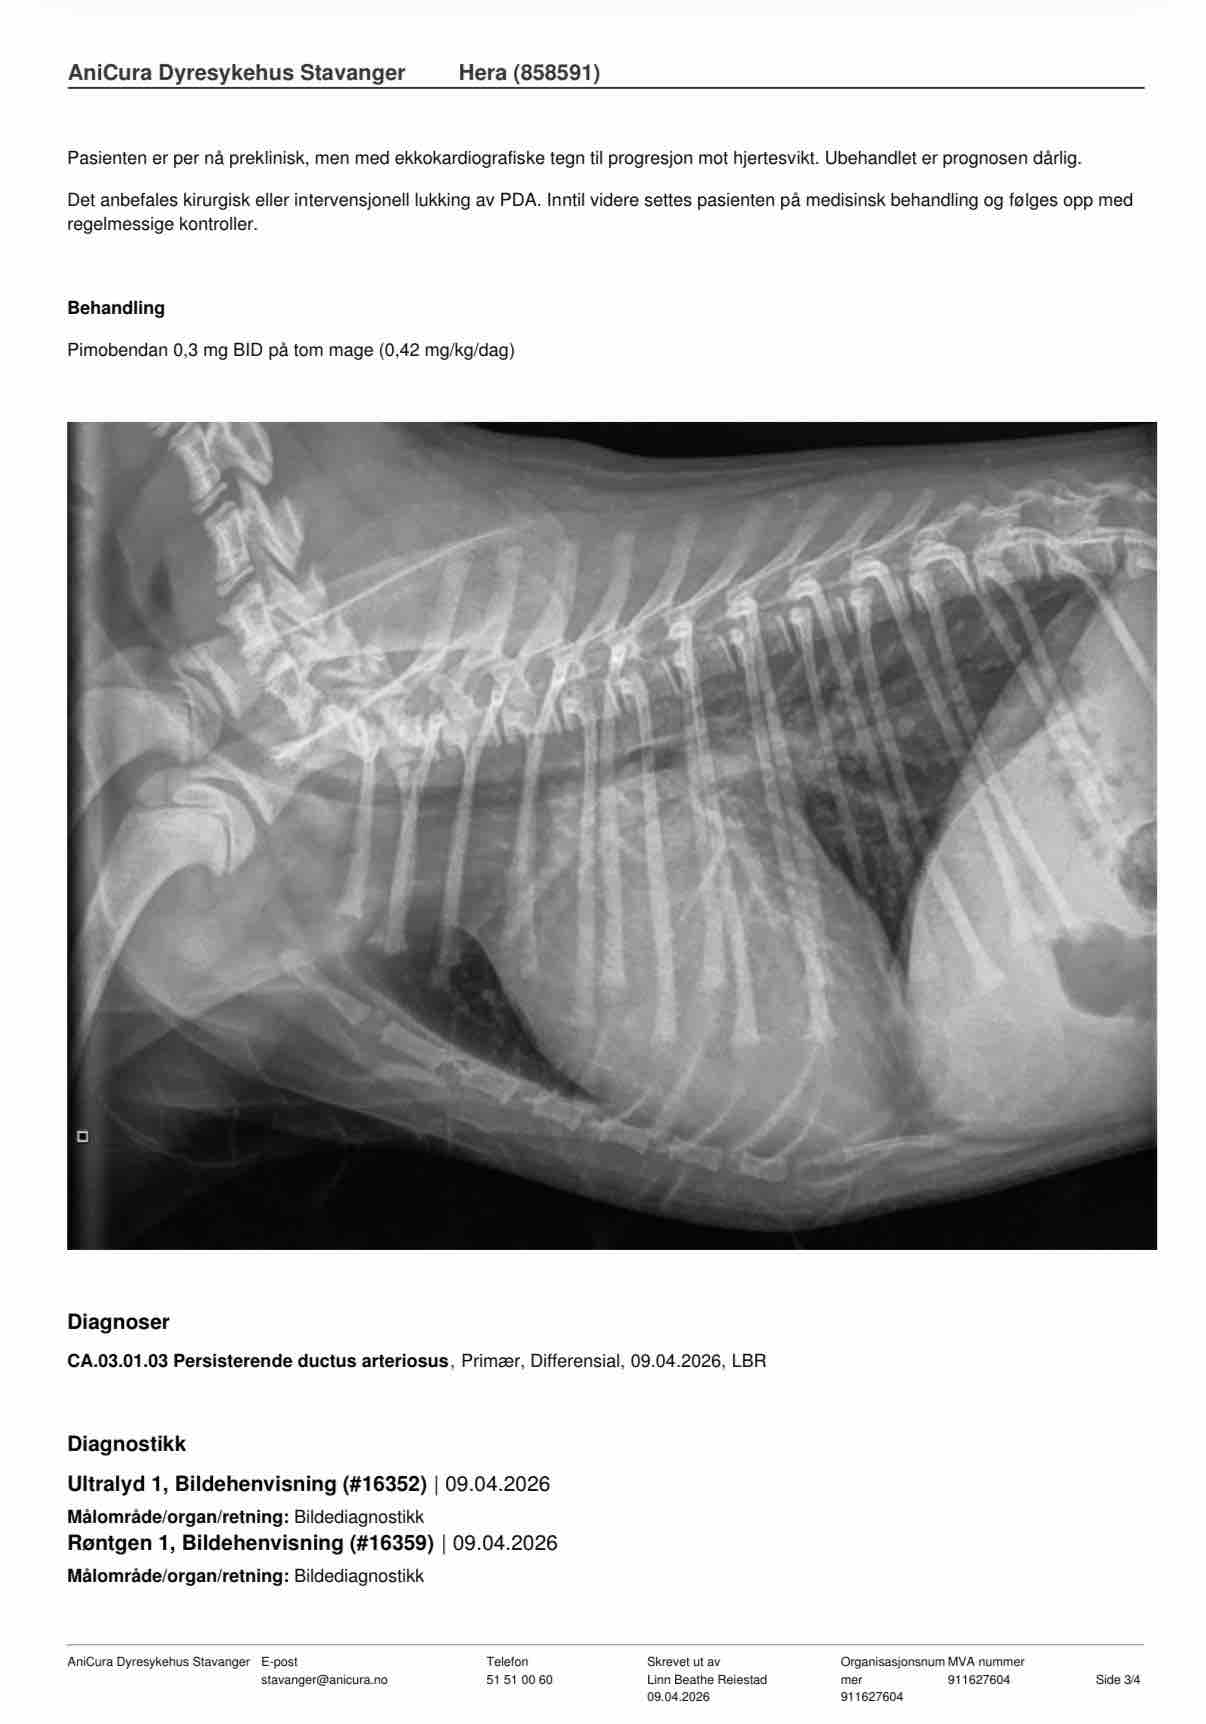

I have a 3-month-old puppy who has sadly been diagnosed with a heart condition called PDA

This means she was born with a part of her heart that didn’t close properly. Because of this, her heart is working much harder than it should, and it is starting to become enlarged.